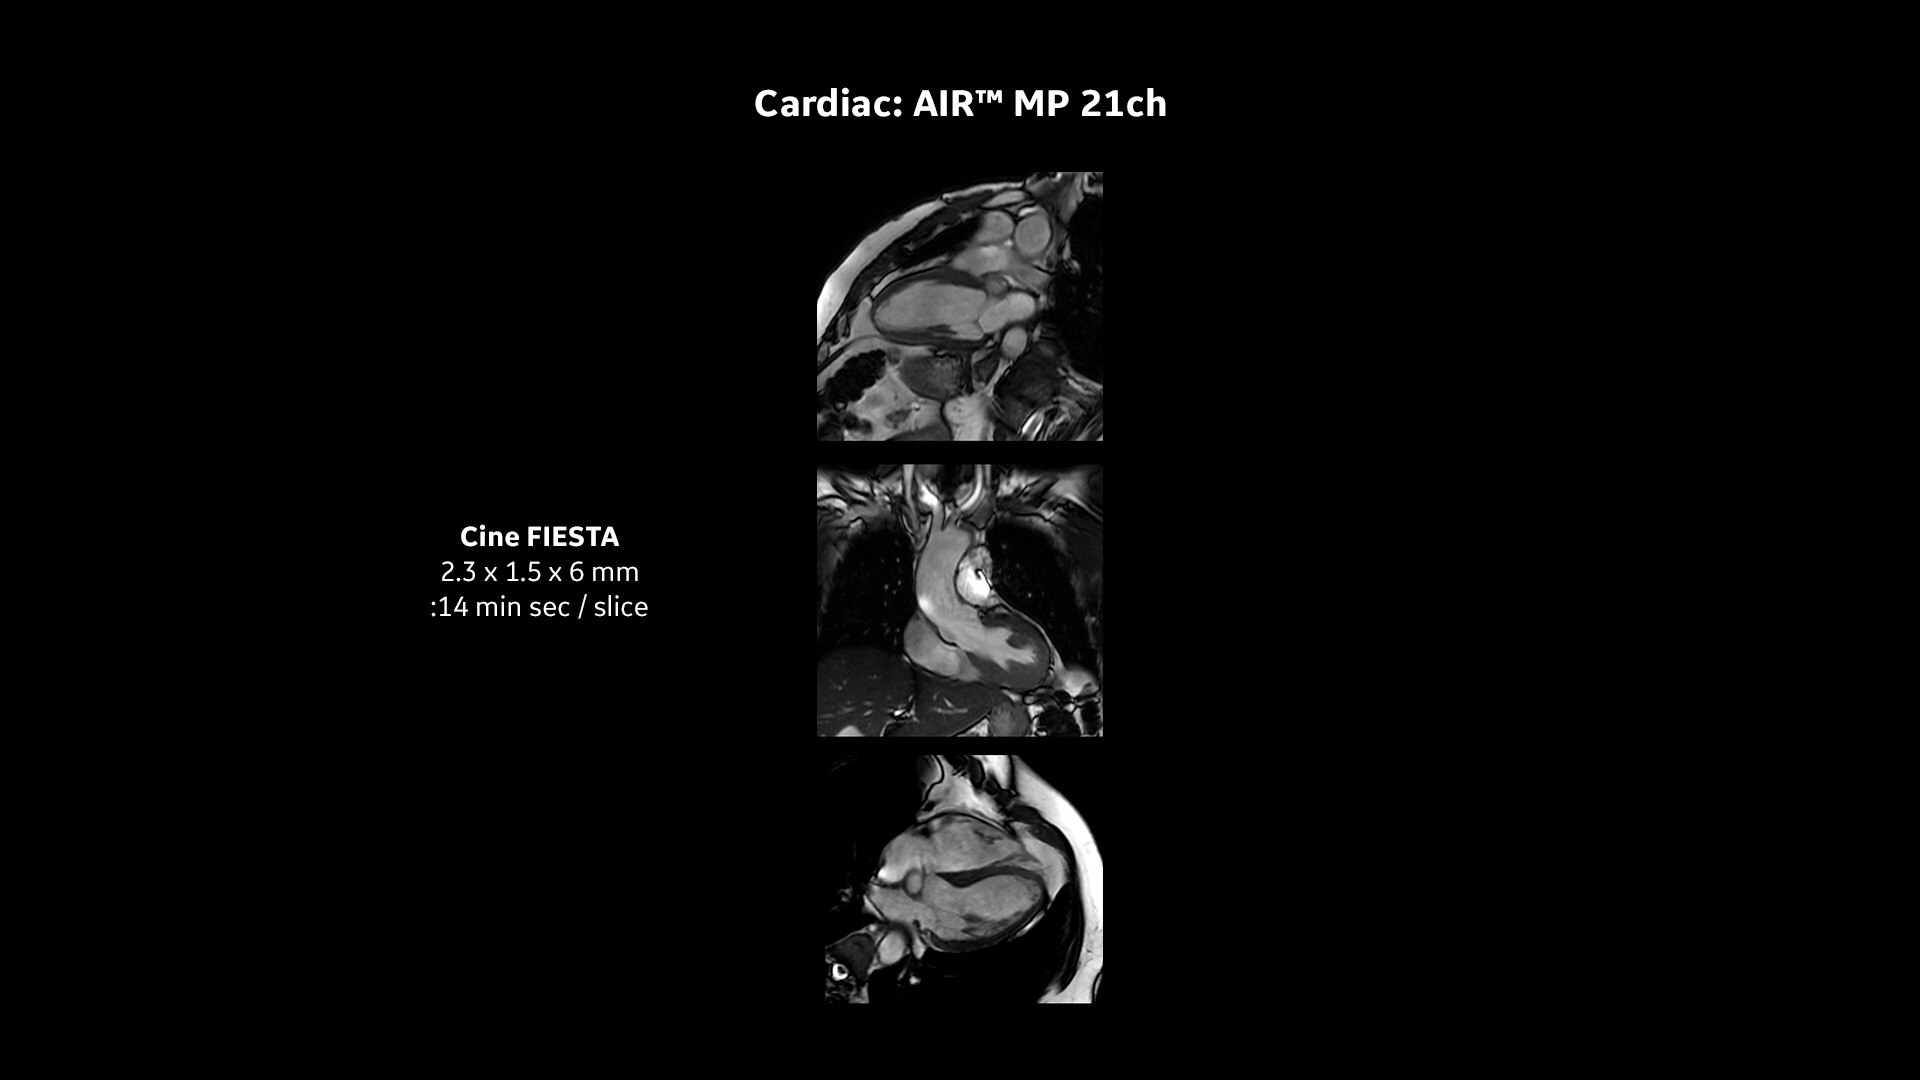

Every step of our cardiac MR assessment is compatible with our pioneering deep-learning algorithms, including: morphology, function, perfusion, mapping and myocardial viability with late enhancement.

Your teams can capture clarity with AIR™ Recon DL, a revolutionary technique to boost image quality, providing accurate anatomic information and advanced soft tissue contrast. It’s already transformed the lives of millions of patients worldwide since 2021. Thanks to Sonic DL™ they can also now assess cardiac viability faster than ever before, with as little as 15 to 20 minutes per scan.*†